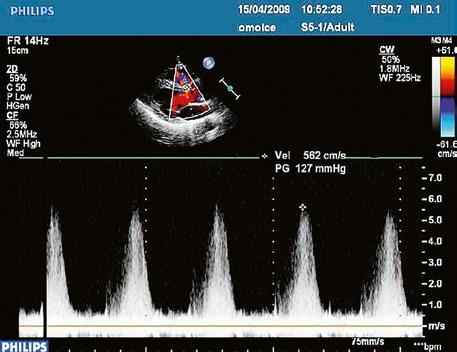

Echokardiografie a jícnová echokardiografie (TEE) je hlavní diagnostickou metodou se zhodnocením morfologie chlopně (Obr. 45.36, Obr. 45.37, Obr. 45.38, Obr. 45.39, Video 45.38), pravé komory (Obr. 45.44) i gradientu (Obr. 45.45). Samotný gradient může být při nevhodném úhlu podhodnocen a je třeba ho korelovat s gradientem na trikuspidální regurgitaci. V dospělosti může mít i významná PS nižší gradient při dysfunkční

Obr. 45.45 Těžká, dlouhodobě neřešená valvární a subvalvární stenóza plicnice s vysokým gradientem 155/82 mmHg (CW doppler) (viz též Obr. 45.44)